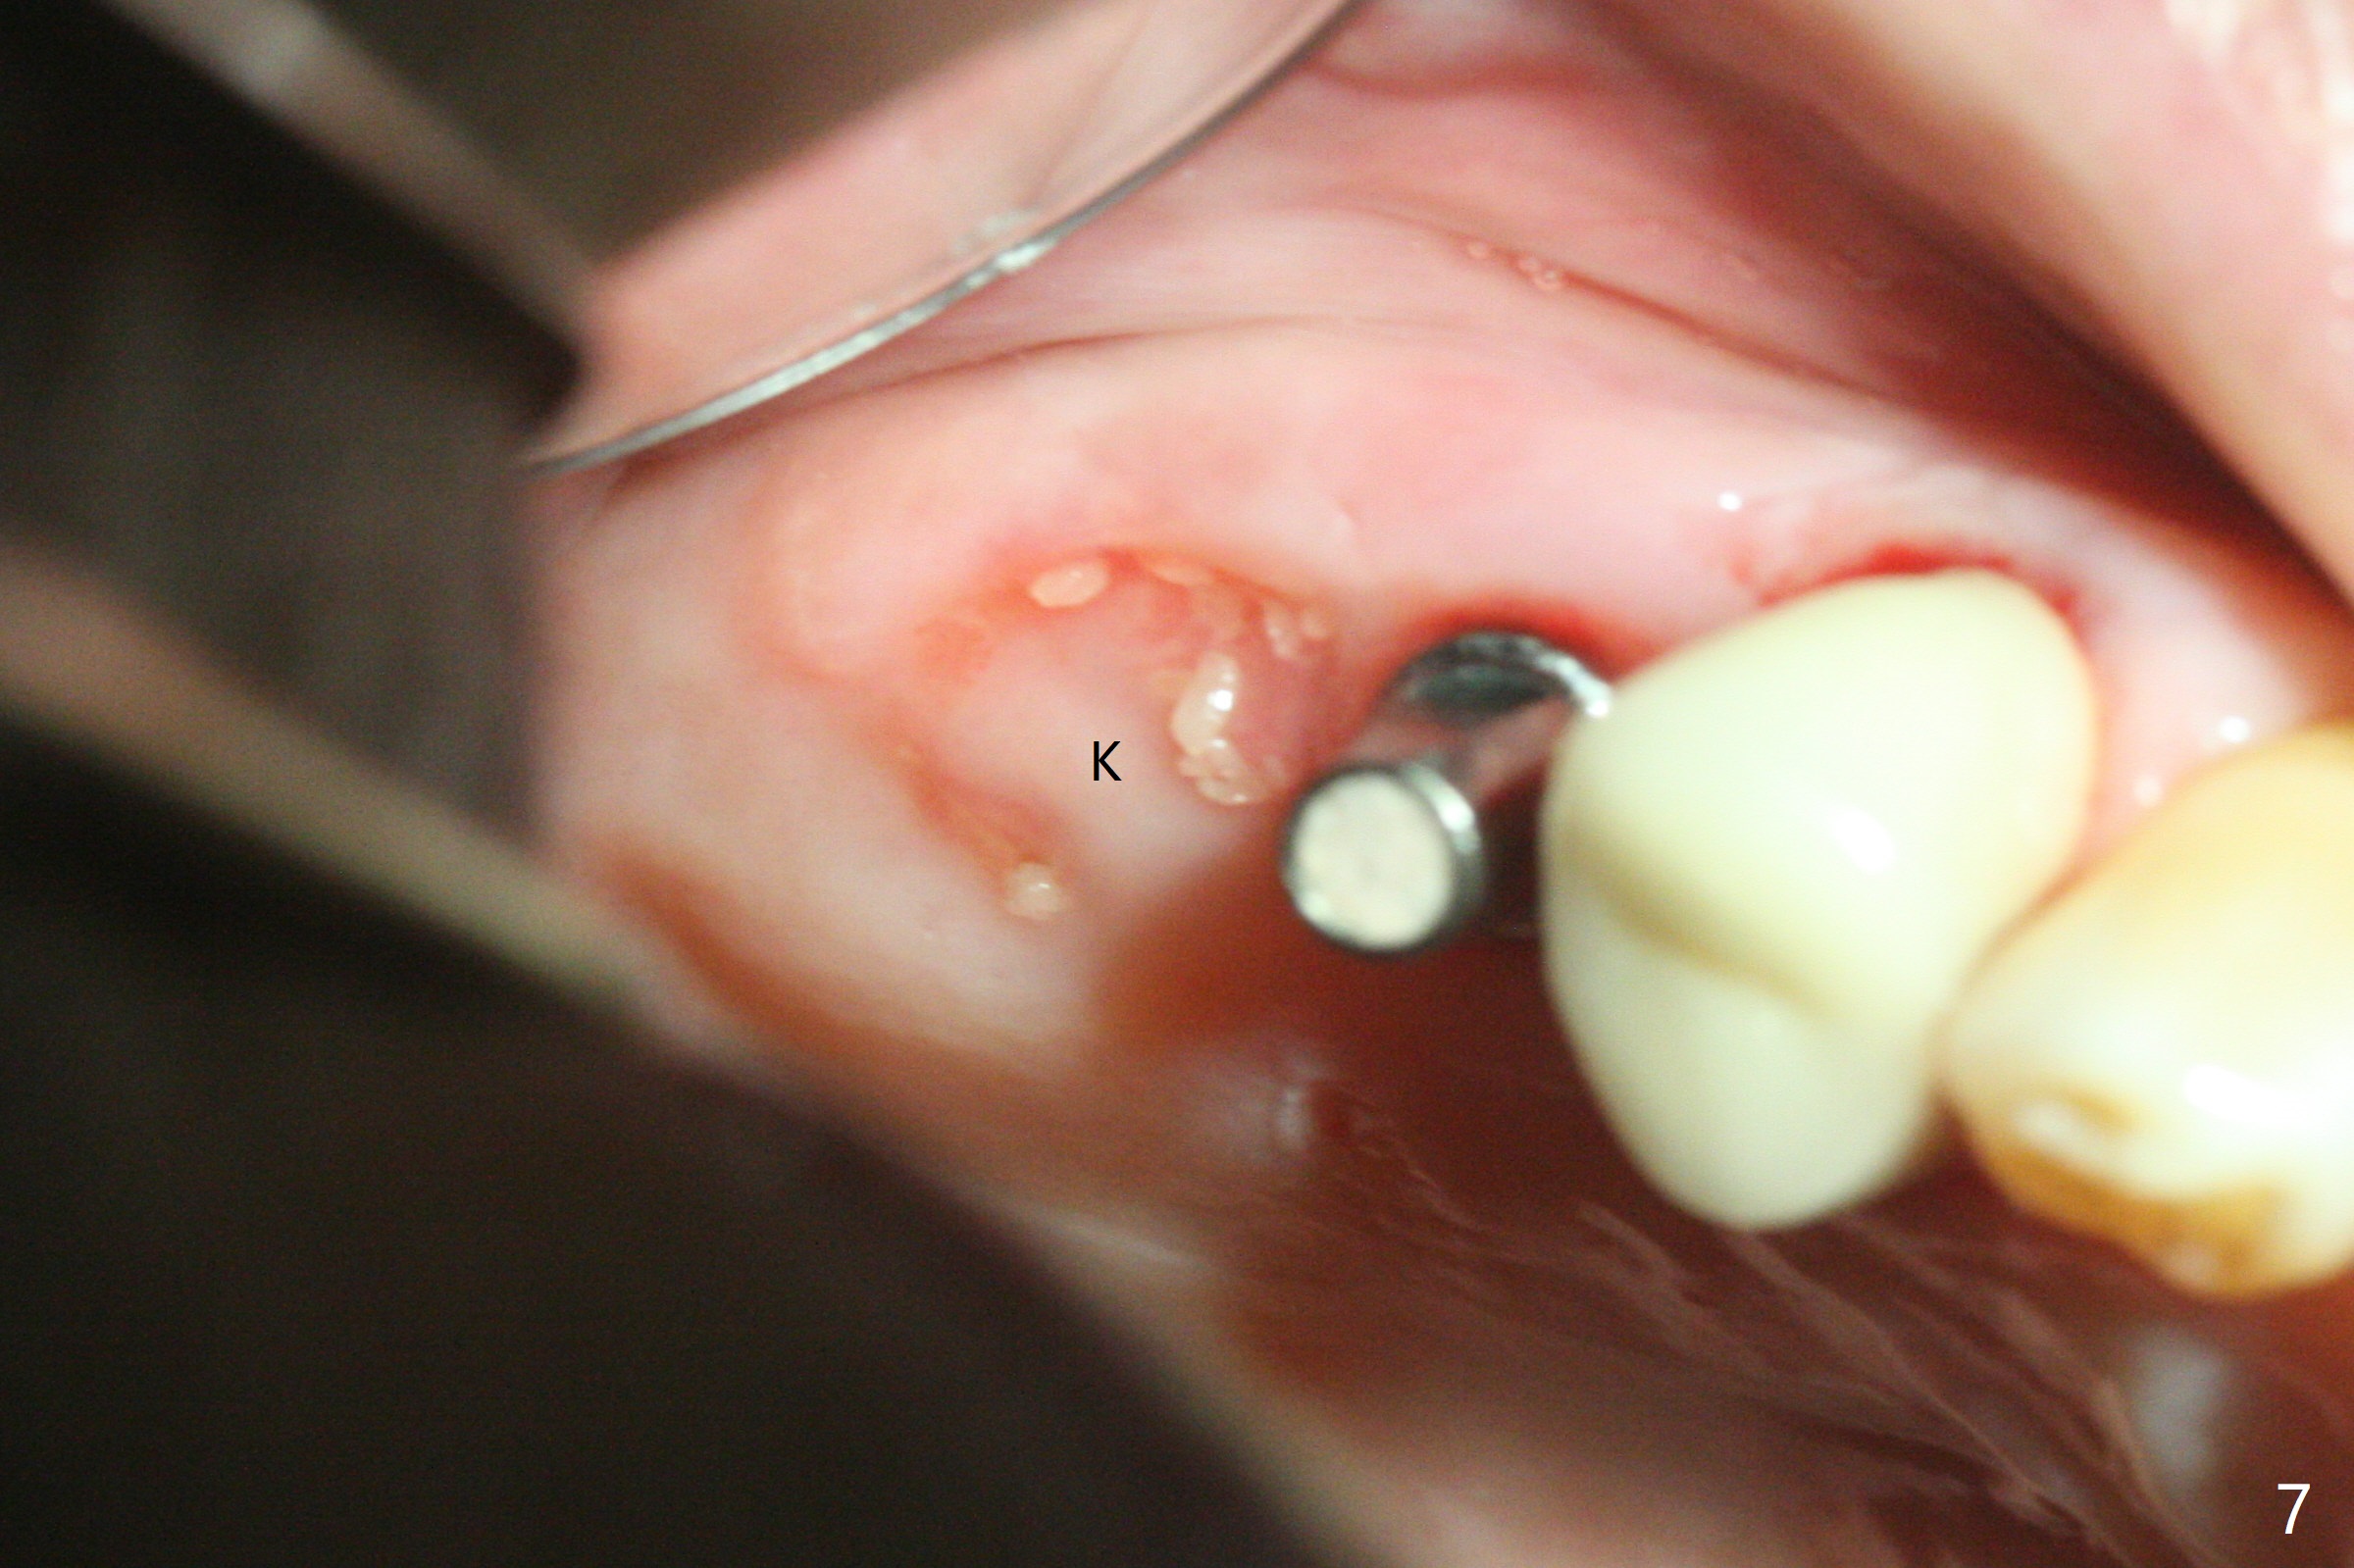

The patient returns for #4 extraction and immediate implant the 1st day clinic reopening after coronavirus lockdown. To reuse autogenous bone for #4 buccal gap closure, delayed implants are also placed at #13 and 14. It is much easier to determine the placement level of the immediate implant (open socket) with guide than that of the delayed ones (flapless) clinically. Immediate postop CT is taken for implant placement level confirmation (Fig.1-3). In fact the autogneous bone is too soft to be packed into #4 socket gaps. It has to be mixed with allograft to be packable. There is oozing when #14 healing abutment is placed. The hemorrhage is severe 4 days postop. The healing abutment is replaced by a healing screw. Hemostasis is achieved when the access is closed with GEM Cap and 4-0 Chromic gut suture. The patient will return for #3 extraction and socket preservation 1 month postop (Fig.4). To prevent postop hemorrhage, a cemented or temporary abutment will be placed at #4 before anesthesia, while .5 or 1.0 cc Augma bone will be placed at #3, covered with collagen plug and acrylic. In fact he cancels the appointment once because of symptom relief and will return 2 months postop. Sticky bone (Fig.5 *) and PRF is used at #3 for hemostasis, while a 5x5.7(3) mm pair (final) abutment is used to hold acrylic dressing in place. The latter remains in place with good oral hygiene 1 month postop (Fig.6 A: abutment). When the acrylic dressing is removed, the socket heals (Fig.7 K: the gingiva between the buccal and palatal sockets when the tooth was removed). The patient returns for impression 4.5 months postop. When the 5x5.7(3) mm abutment at #4 is reseated after cleaning, there is no horizontal gap between the abutment and implant in BW (Fig.8), while there is in PA (Fig.9). When a smaller abutment is seated (Fig.10), there appears to be a horizontal gap, whereas there is no vertical one. The situation is the same with #13 (Fig.11,12). The common denominator is 3.5 mm implant. With suspicion, BW is taken for the implant at #4 immediately before cementation (Fig.13). It appears that the abutment is most likely seated completely. There is no bone loss or screw loosening 4 months post cementation (Fig.14,15). One month later the patient agrees to have 3 lower implants to replace RPD.